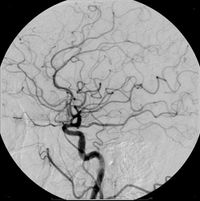

تستخدم المواد المظللة في التشخيص الطبي، لتشخيص تغيرات تحصل في أعضاء معينة في الجسم كالأوعية الدموية مثلاً التي هي في حالتها الطبيعية ممتلئة بالدم، الذي له كثافة إشعاعية مشابهة لكثافة النسيج المحيط (عضلات أو أنسجة رابطة) وبالتالي لا يمكن رؤية الأوعية الدموية على صورة الأشعة. فيتم حقن المادة الملونة في هذه الأوعية الدموية، مما يرفع الكثافة الشعاعية للمحتوى الوعاء الدموي ـ هنا على سبيل المثال ـ ويجعل محتوى هذا الوعاء ومساره واضحاً. كما هو مبين في الصورة التي تظهر القسطرة. وهذا المبدأ يمكن استخدامة في إظهار محتويات كثير من "الأوعية" في جسم الإنسان، مثل الجهاز الهضمي أو المثانة والمجاري البولية ... الخ.

مثالٌ آخر على المادة المظللة، هنا حُقنت المادة المظللة في الأوعية الدموية الدماغية، وظهرت بشكل واضح، شاهد أيضاً القسطرة الشريانية